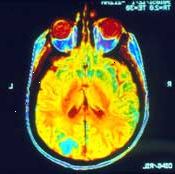

Magnetická rezonance (MRI)

MRI může být použit k určení, zda rakovina se rozšířila do hrudníku nebo mozek. Pokud tomu tak je, MRI může také ukázat, velikost a rozsah šíření. Váš lékař může také požádat o MRI v případě, že výsledky rentgenu nebo CT nemají jasně dát odpověď. V některých případech budete injekci s kontrastní barvou přímo před získáním kontroly. Pro tento test, budete ležet na stole, jak to prochází skenerem. Počítač používá data z magnetických vln vytvořit velmi detailní obrazy uvnitř vašeho těla. Každý obrázek může trvat 2 až 15 minut, takže celý zážitek může trvat hodinu nebo více. Tyto obrázky mohou ukázat rozdíl mezi normální a nemocné tkáně. Tento test je bezbolestné. Zeptejte se na špunty do uší, protože tam je hlasitý hluk dunění během kontroly. Pokud máte klaustrofobii, můžete před tím, než tento test potřebují sedativa.